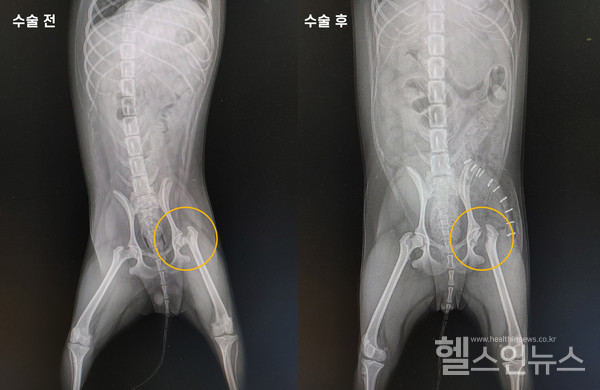

(dhlsWhrqnxj)대퇴골두제거수술전,후X-레이사진

대퇴골두허혈성괴사는 진통제나 붕대, 레이저 치료 등을 통한 내과적 치료법도 가능하기는 하지만 가장 근본적인 치료 방법은 외과적인 수술을 진행하는 것이다. 대퇴골두제거수술(FHNO, Femoral Head&Neck Ostectomy)은 대퇴골두를 반듯하게 잘라내는 수술이다. 보행에 사용하는 관절을 제거하면 어떻게 걷는지 묻는 보호자들이 있다. 수술 후 주변의 섬유조직이 대퇴골두의 역할을 대신해 수술한 뼈를 충분히 지지해 준다. 따라서 보행에는 전혀 문제가 생기지 않는다. 하지만 대퇴 근육이 많이 위축된 상태라면 수술을 진행해도 예후가 좋지 않을 수 있다. 따라서 대퇴골두허혈성괴사는 수술 후 관리도 중요하다. 고관절 주변 근육과 조직의 힘으로 걸을 수 있을 때까지 무리한 움직임은 피하고 재활을 통해 근육이 충분히 회복할 수 있도록 해야 한다.